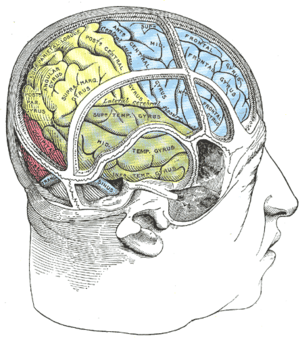

Lateral surface of left cerebral hemisphere, viewed from the side.

Lateral surface of left cerebral hemisphere, viewed from the side. Drawing to illustrate the relations of the brain to the skull.